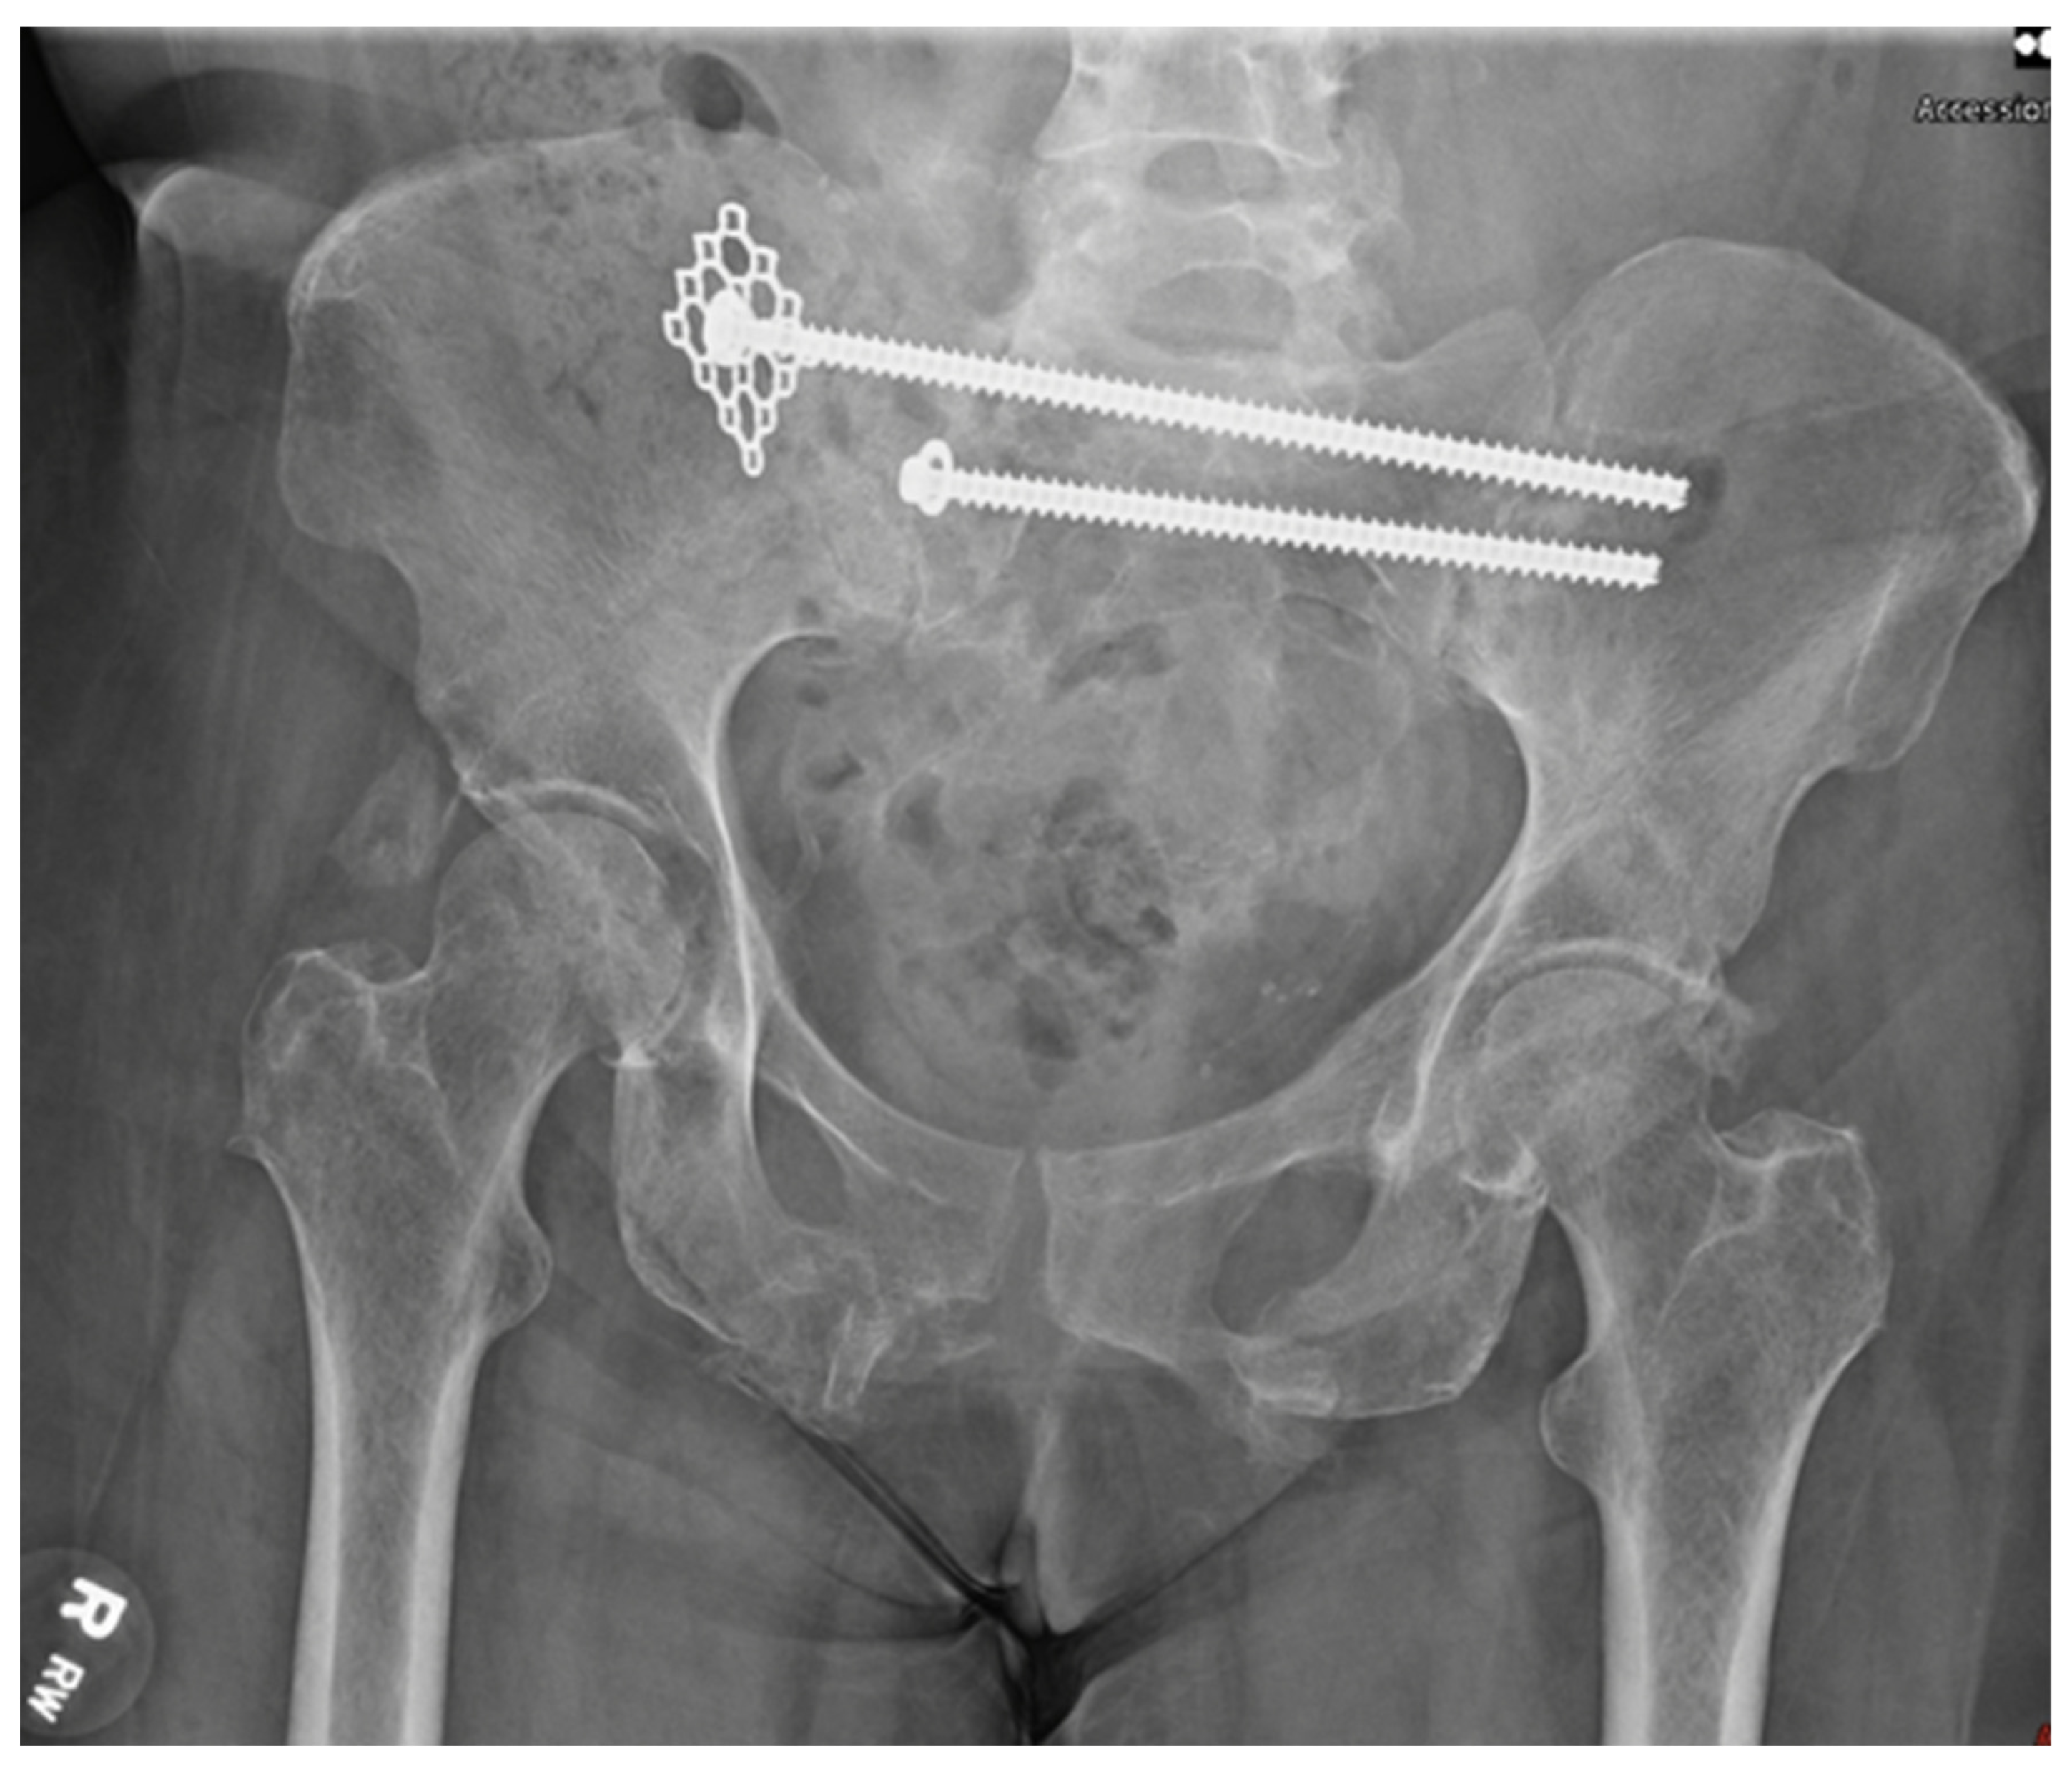

A 59-year-old female with no known past medical history presented to our level 1 trauma center, having been involved in a rollover motor vehicle collision. Plain radiographs and CT imaging demonstrated various orthopedic injuries including a Dennis type 1 vertical shear sacral fracture, bilateral superior and inferior pubic rami fractures (Figure 1 and Figure 2), right T5–T6, L1–L5, and left L2–L3 transverse process fractures, spinous process fractures of T7 and T9, and right posterior rib 4–7 fractures. Additional, non-orthopedic injuries included pneumothorax, retroperitoneal hematoma, grade 4 hepatic injury, grade 3 splenic injury, and grade 2 kidney injury. On day 3 of presentation, the patient was stable enough for operative fixation from the orthopedic surgery team.

Figure 1.

The original injury film on an AP pelvis in a skeletally mature individual demonstrating a vertical shear sacral fracture, bilateral superior and inferior pubic rami fractures.